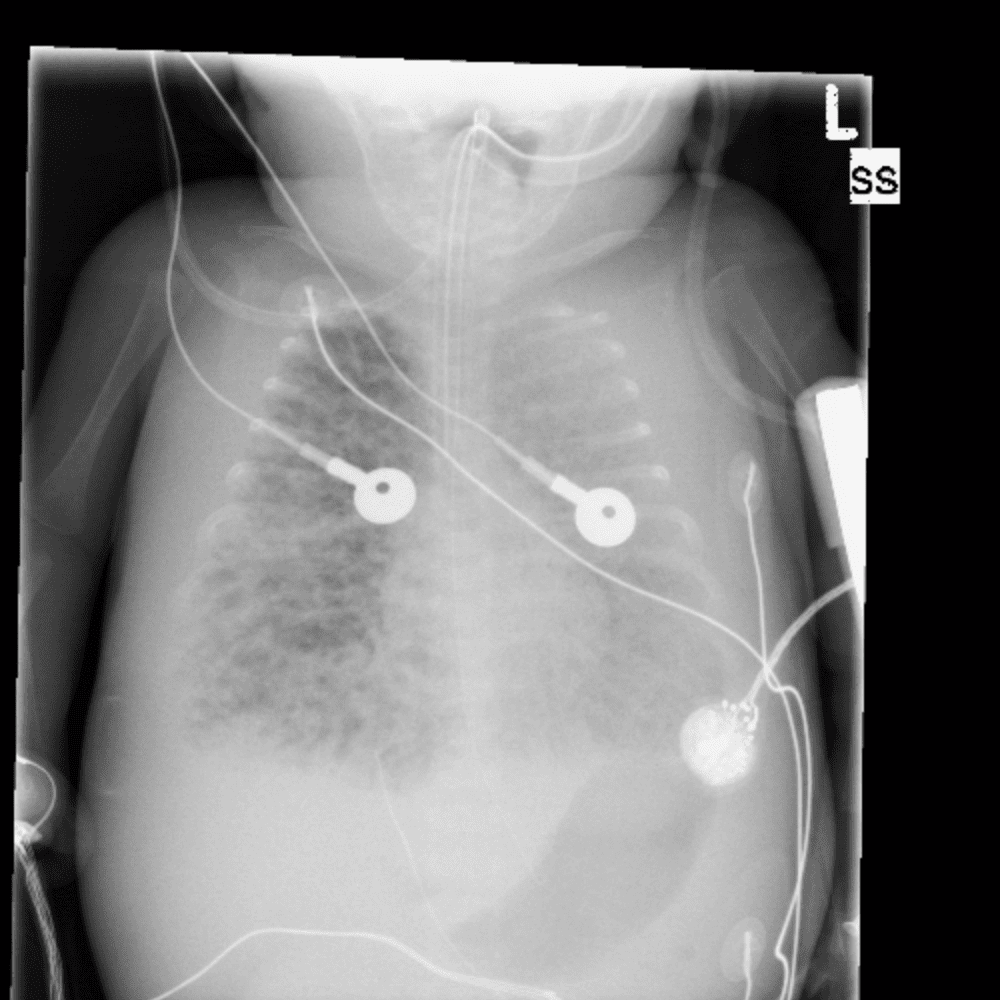

Peds Chest

Practice

Simulates call by including subtle or difficult cases and some normals.

50 cases